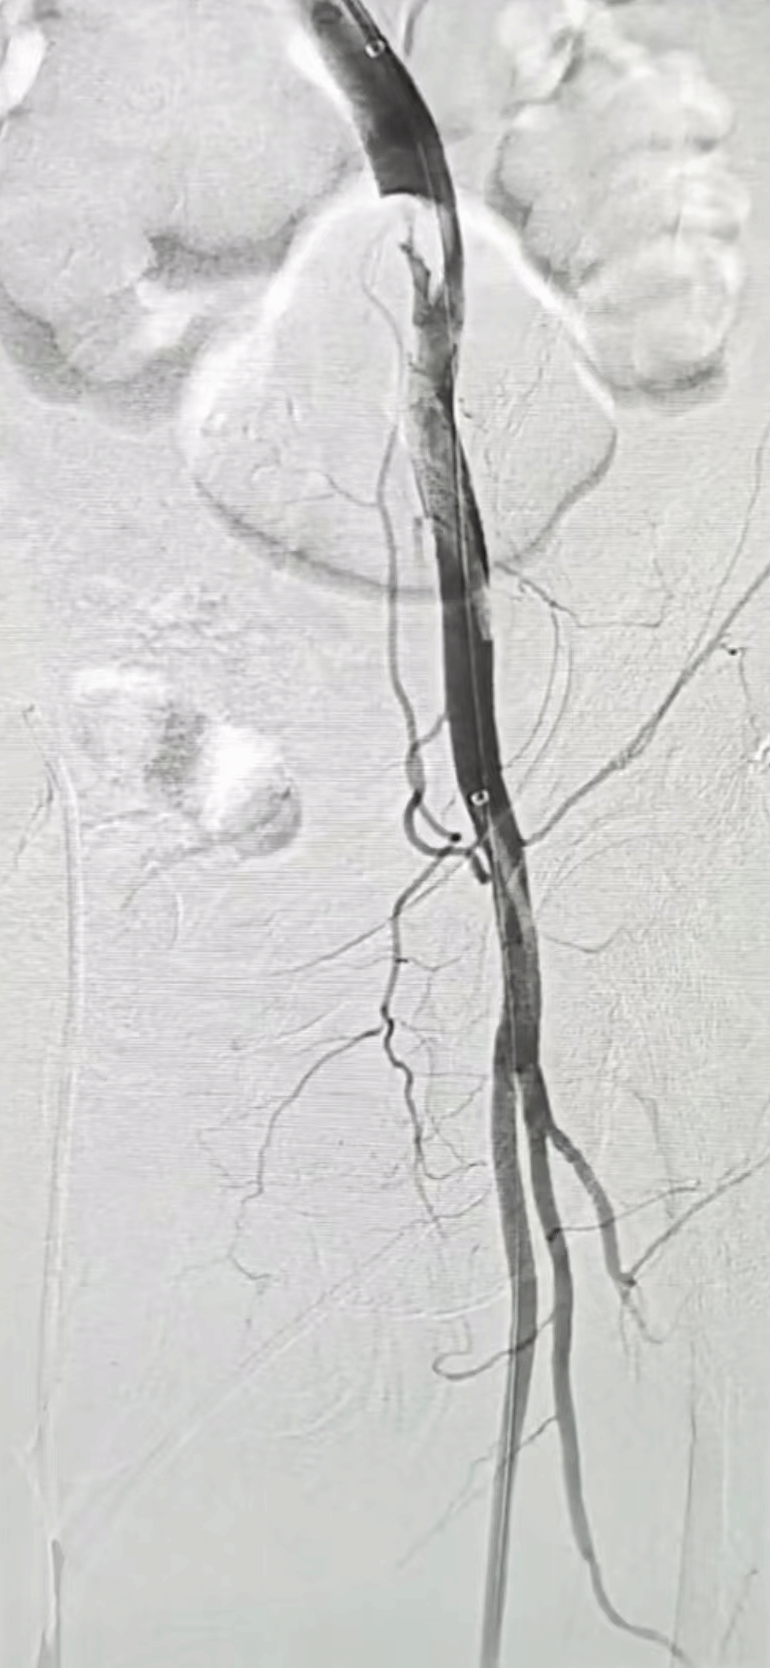

患者术前造影患侧肢体血管完全不显影

开通后的患侧动脉造影